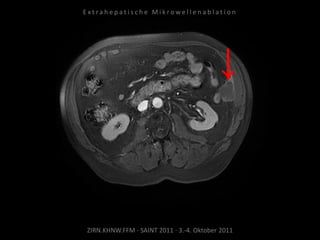

Bildgebung vor MWA:

CT vom 14.07.2010

Metastase lateral der linken Niere

nahe Colon descendens progredient.

Situation:

Metastasierung über längeren Zeitraum

lokal begrenzt,

1 Metastase progredient.

Organnahe Lage in unmittelbarer

Nachbarschaft zur linken Niere bzw. zum

Colon descendens.